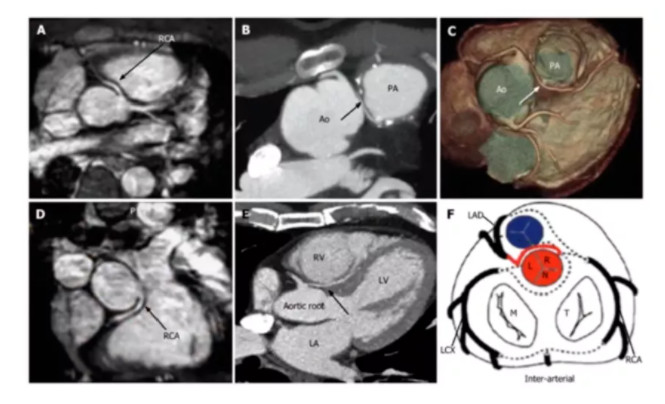

冠状动脉起源异常

LCX起源右窦:

LAD起源右窦: